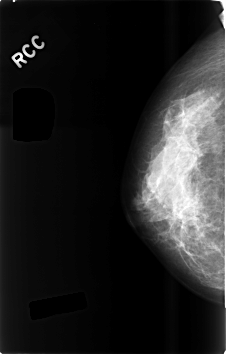

C_0494_1.RIGHT_CC

RIGHT_CC LINES 4600 PIXELS_PER_LINE 2928 BITS_PER_PIXEL 12 RESOLUTION 50 NON_OVERLAY